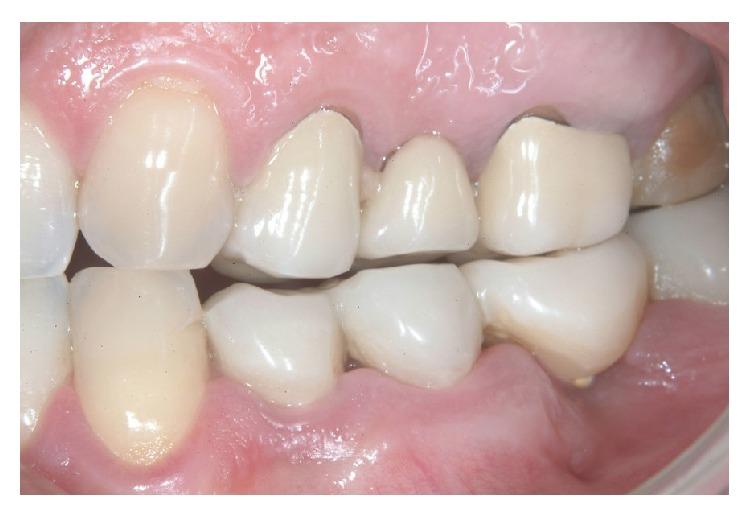

The extraction of teeth results in rapid bone resorption both vertically and horizontally in the first month. The loss of alveolar ridge reduces the chance of implant rehabilitation. Atraumatic extraction, implant placement in extraction socket, and an immediate prosthesis have been proposed as alternative therapies to maintain the volume and contours tissue and reduce time and cost of treatment. The immediate load of implants is a universally practiced procedure; nevertheless a successful procedure requires expertise in both the clinical and the reconstructive stages using a solid implant system. Excellent primary stability and high bone-implant contact are only minimal requirements for any type of implant procedure. In this paper we present a case report using a new type of implants. The new type of implants, due to its sophisticated control system of production, provides to the implantologist a safe and reliable implant, with a macromorphology designed to ensure a close contact with the surrounding bone.